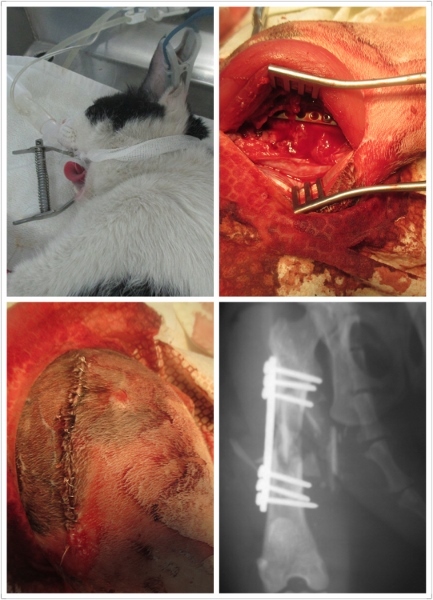

主題: 疑似被撞傷的小熊 申請者姓名: 李英儒 花色: 申請日期: 2015-05-18 21:46:41 申請者部落格: 申請者臉書網址: https://www.facebook.com/profile.php?id=100000352503503 所在縣市/合作醫院: 高雄市/樂生動物醫院 治療費用: 29700元 需求人數: 32人 已結案 (2022-03-11 00:07:29) 報名人員: orange(已付款)、Ficus Hsu(已付款)、Avril Hsu x2(已付款)、geniuscan(已付款)、Irena、misselaine(已付款)、Po-Lin Chen(已付款)、Po-Lin Chen x2(已付款)、Frankie(已付款)、游佳雯(已付款)、vivian(已付款)、BigMao、川之光(已付款)、陳魚寶(已付款)、coby0427(已付款)、Polly Ma x2(已付款)、rainbowstar39(已付款)、Little Cat Chang(已付款)、篝(已付款)、Abigail Cheng、lunyi(已付款)、lunyi(已付款)、lunyi(已付款)、lunyi(已付款)、Lia x2(已付款)、阿胖 x2(已付款)、Mickey Han(已付款)、Kate x2(已付款)、蔡小花(已付款)、 候補人員: 動物病情說明: 在餵養區內的親人的孩子小熊,原本是出現一些小外傷,以為跟附近的貓打架,不以為意,直到4/6放飯時間,左後腳無法著地,因為可以摸的到,所以急忙回家拿布跟外出籠撈起後,4/7早上送高雄 樂生動物醫院

樂生動物醫院判定

左後腳股骨粉碎性骨折,右後腳股骨頸斷裂,身上亦有一些外傷,有齒齦炎,口炎及輕微結膜炎等鼻氣管炎症狀,初步驗血有嚴重發炎(白血球過高)及肝臟受損(ALT及ALKP過高)的現象且有脫水,初步先點滴至及藥物治療待發炎及肝指數有下降後再另行骨科手術,

右後腳骨斷列部份討論後,有機會能自行癒合,不是急迫性手術,所以尚待評估,

4/20~4/23 術後恢復期